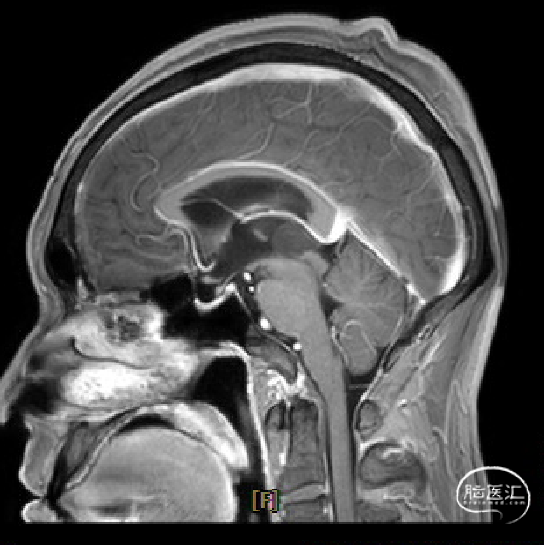

患者5年前无明显诱因出现阵发性头晕,无明显头痛、恶心呕吐等不适,开始未予重视,2022-7-19出现头晕加重,伴视力下降,遂于2022-7-24在当地医院行颅脑MRI提示:松果体区肿瘤伴梗阻性脑积水。

于该院在2022-7-27全麻下行松果体区病灶部分切除活检+神经内镜下第三脑室底造瘘术,术后由于取出肿瘤组织少,未能明确病理结果。患者术后恢复顺利,为进一步治疗就诊于我院。

枕下后正中开颅经幕下小脑上入路松果体区肿瘤切除术。

术前MRI与术后复查MRI对比